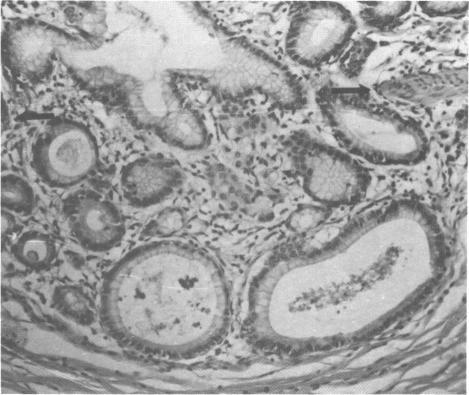

In a series of experiments, rhesus monkeys have been given in their diets 0.3, 1.5, and 25 ppm of a commercial polybrominated biphenyl (PBB) (as FireMaster FF-1). The seven adult female monkeys receiving 0.3 ppm PBB have been on the treatment regime for 15 months and have consumed over 22 mg of PBB. During the initial 6 months of exposure, they lost weight and 2 of the animals develop sterile abscesses. At 6 months, 4 of the 7 animals had flattened and lengthened serum progesterone peaks. This change was correlated with an increase in length of their menstrual cycles. After 6 months of PBB exposure, the animals were bred. Two of the 7 animals showed excessive and prolonged implantation bleeding. Two abortions and 5 live births were recorded. All of the experimental infants were smaller than the controls at birth. The animals receiving a diet containing 1.5 ppm PBB for 36 weeks (total intake 70 mg) have shown a moderate weight loss and decrease in serum cholesterol. Similar changes have also been recorded in the group given the 25 ppm PBB diet for 14 weeks (approximately 500 mg total intake). In addition, these animals have also developed a hyperplastic gastritis.

在一系列实验中,给恒河猴的饮食中添加了0.3、1.5和25 ppm的一种商业多溴联苯(PBB)(商品名为FireMaster FF - 1)。接受0.3 ppm PBB的7只成年雌性猴子已接受该治疗方案15个月,摄入的PBB超过22毫克。在最初接触的6个月里,它们体重减轻,其中2只动物出现无菌性脓肿。6个月时,7只动物中有4只血清孕酮峰值变平且延长。这种变化与它们月经周期长度的增加相关。PBB暴露6个月后,这些动物进行了繁殖。7只动物中有2只出现过度且持续时间长的着床出血。记录到2次流产和5次活产。所有实验婴儿出生时都比对照组小。接受含1.5 ppm PBB饮食36周(总摄入量70毫克)的动物出现了中度体重减轻和血清胆固醇降低。在给予25 ppm PBB饮食14周(总摄入量约500毫克)的组中也记录到了类似变化。此外,这些动物还患上了增生性胃炎。